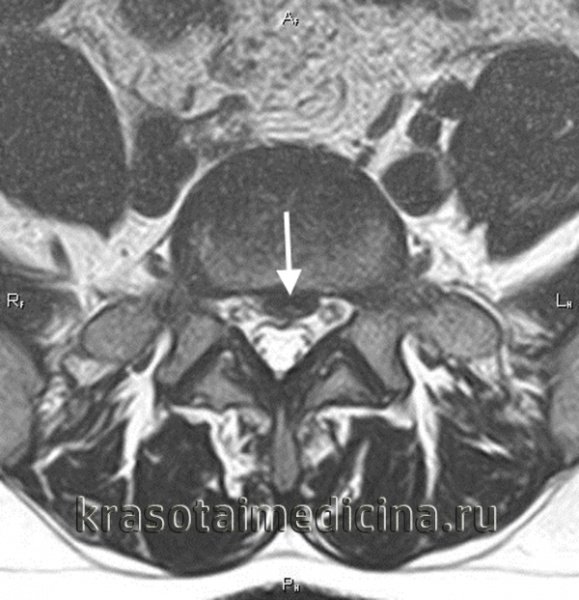

Тут, друзі, все трохи складніше, ніж просто біль у спині. Діагностика корінцевого синдрому включає в себе різноманітні методи обстеження. Тут є і МРТ, і КТ, і навіть простий рентген. Але іноді все починається зі звичайної бесіди з лікарем і перевірки рефлексів.

- Грижа диска: Це, мабуть, найочевидніша причина. Часто, коли диск виштовхнутий за межі своєї оболонки, нерв стає заклиненим.